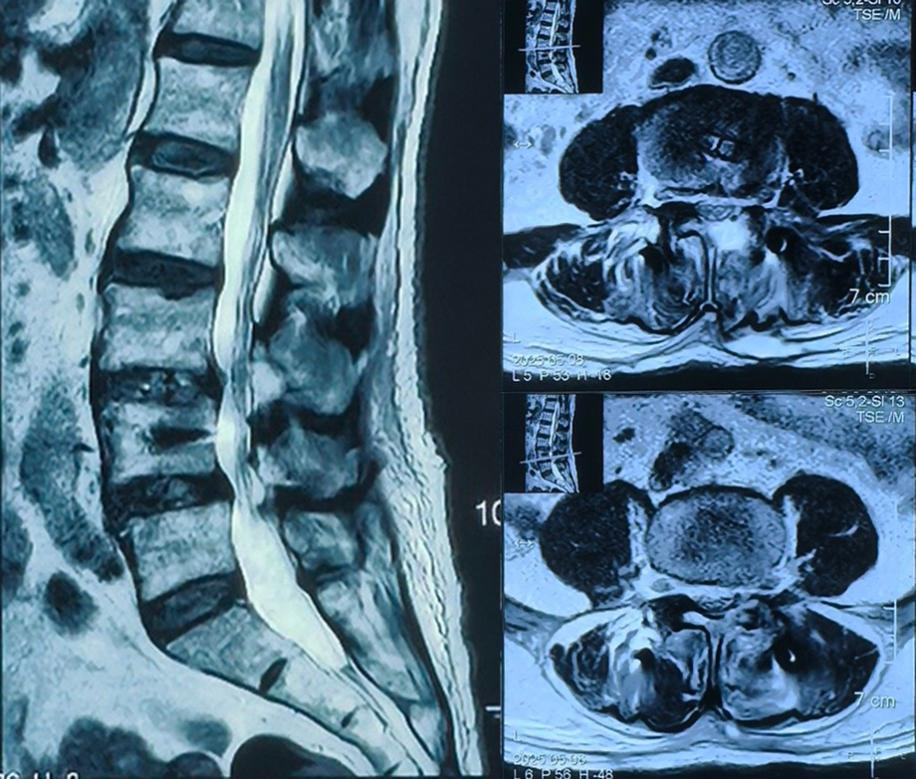

术中显示:双节段双侧减压,硬膜囊和双侧神经根压迫解除

术后核磁:神经受压解除,硬膜囊膨隆